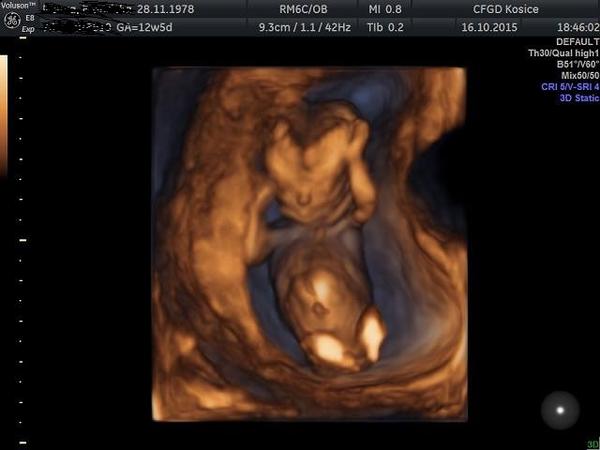

Dnes som bola na kontrole.Vraj to je akrobatka,nožičky mala vystreté,chodidlá za hlavou.ale v tomto období často menia polohu,všelijako,majú ešte dosť miesta.